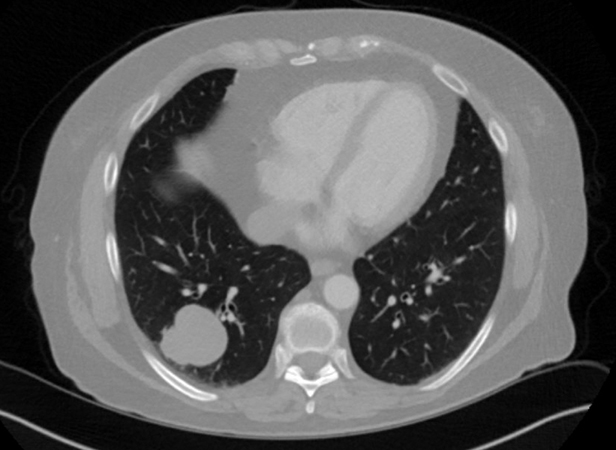

Clinical History:A 70-year-old woman, never-smoker, presented with right upper quadrant abdominal pain and nausea. She had no known oncologic history. CTA chest showed a polylobular solid nodule in the right lower lobe measuring 3.9 cm (Figure 1). PET scan showed mild metabolic activity within the lung nodule (maximum SUV of 4.5), and no other sites of abnormal metabolic activity. A CT-guided biopsy was performed (results not shown), and she subsequently underwent a thoracoscopic right lower lobectomy. Gross examination revealed a well-circumscribed, tan-white, firm nodule that detached from the lung parenchyma during surgical retrieval. Microscopic examination showed a nodular growth pattern with alternating fibrotic and myxoid areas at low magnification (Figure 2). There were several large collagen rosettes with hyalinizing fibrosis (Figures 3 and 4). Higher magnification revealed bland spindle cells arranged in a swirling storiform pattern within fibromyxoid stroma (Figure 5). No increased mitotic activity or tumor necrosis was present. Immunohistochemical stains showed neoplastic cells were positive for MUC4 (Figure 6) and negative for pan-cytokeratin, desmin, SOX10, STAT6, DOG1, and beta-catenin.